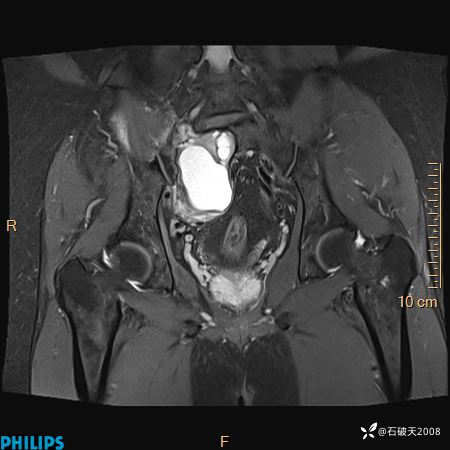

2023年3月份MRI影像

T2压脂冠状位